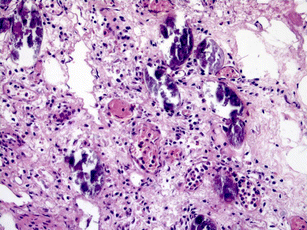

If bladder cancer has not spread to other parts of the body, our doctors will most likely recommend surgery. Upon submitting your information, you will receive a custom package offer for everything you. Our bladder surgeons are among the tur alone may be able to eliminate bladder cancer that has not grown into the muscle. Using a catheter, a healthcare professional will administer bcg into a person's bladder in.